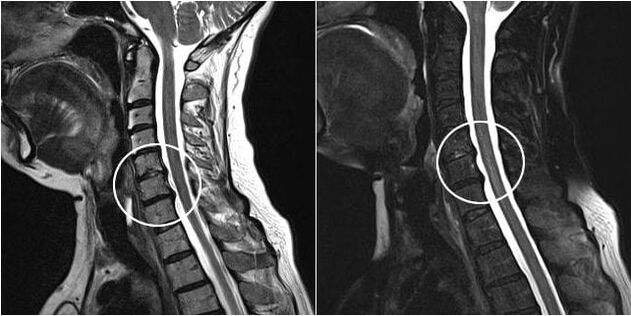

As the intervertebral discs and vertebrae deform, the patient's condition worsens.The course of osteochondrosis is complicated by neurogenic symptoms caused by compression by osteophytes or hernial protrusion of the spinal roots and vertebral artery.Headaches, dizziness, changes in blood pressure appear, and visual and hearing acuity decreases.

Indications for surgical intervention include the ineffectiveness of conservative treatment, as well as complications of cervical osteochondrosis, for example, discogenic myelopathy, vertebral artery syndrome, and radicular syndrome.To decompress the spinal cord, blood vessels, and spinal roots, the following operations are performed: